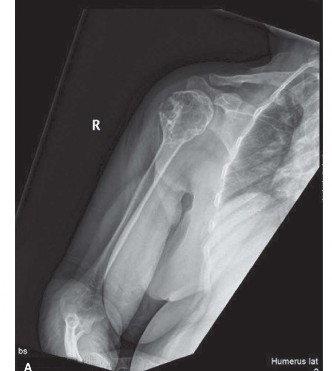

A 71-year-old male is brought to the ER after sustaining a motor vehicle crash. During routine trauma workup,…